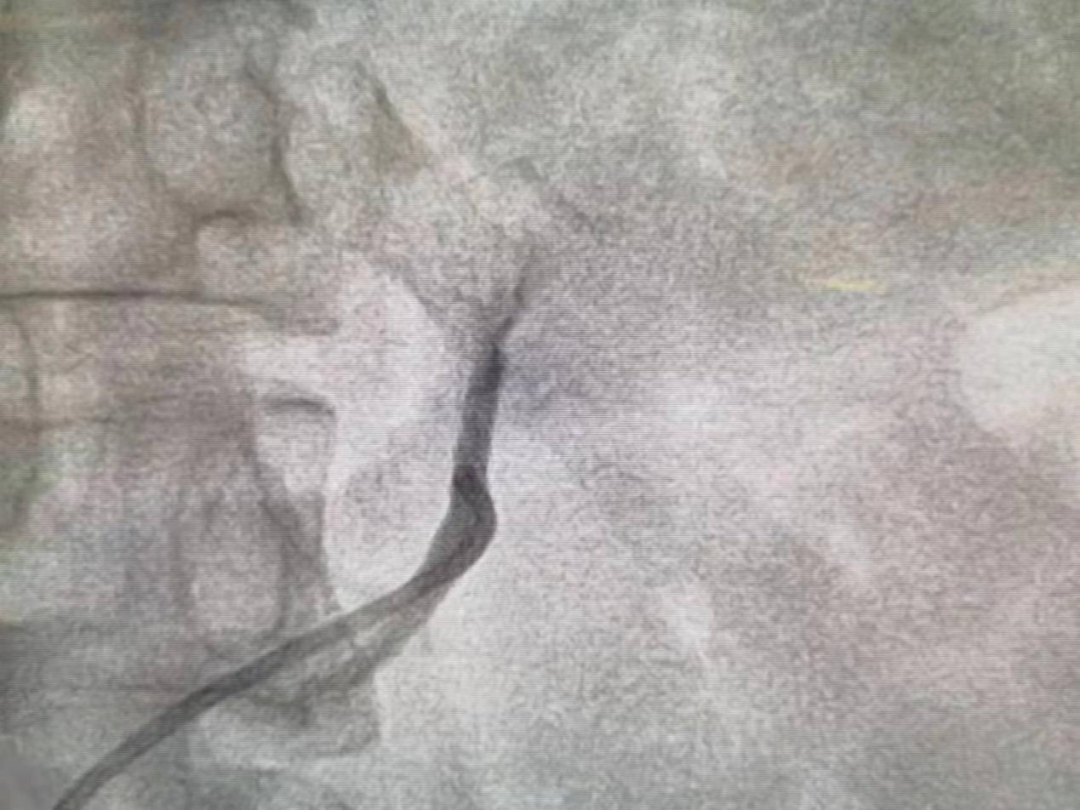

经典的AVS一般采用股静脉入路,近年国家心血管病中心阜外医院蒋雄京教授发展了经肘静脉的入路,使AVS的学习曲线明显缩短。既往的AVS无论是股静脉入路还是肘静脉入路,均需应用2种或以上的采血导管,采血的成功率和效率仍无法让人满意。

近年,成都医学院第一附属医院心血管内科高血压中心王沛坚教授团队经股静脉入路第一次介绍了一根导管法进行AVS 100余例的报道。

在此之后工作中,王沛坚教授不断改进方法和总结经验,在原来方法基础上进行了改良,90%以上的患者可在10min之内成功完成采血,目前中心已采用该技术完成近500例的AVS,是全球范围内较为成熟的AVS中心。

该方法不但减少了患者和术者的射线暴露,还显著提高了采血的效率和成功率并在最大程度上节约了卫生耗材。王沛坚教授的改良一根导管法行AVS在国内多个学术会议和多个医院进行了推广,得到了同行的认可。